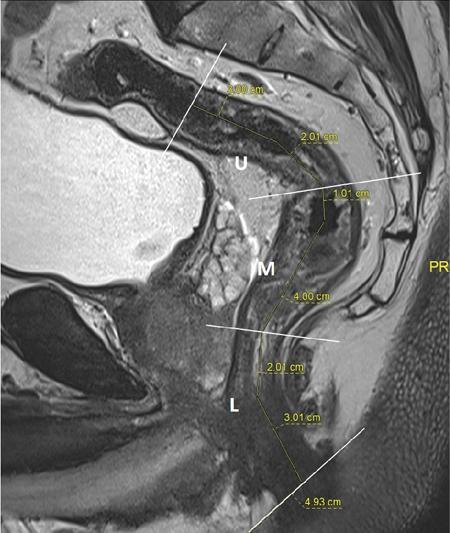

Sumit Mukhopadhyay, Saugata Sen, Aditi Chandra, Argha Chatterjee, Priya Ghosh, Anisha Gehani Cloaca is the part of hindgut caudal to the attachment of the allantoic diverticulum. It divides into a broad anterior urogenital (vesicourethral and urogenital sinus) part and a narrow posterior anorectal compartment/primitive rectum, separated by the urorectal septum. This anorectal compartment gives rise to mid rectum and lower rectum and upper part of anal canal proximal to dentate line. The peritonealized upper part of rectum develops from hindgut proximal to cloaca. The distal most part of anal canal below the dentate line develops from invaginated ectoderm known as proctodeum (Fig. 8.5.1). Initially during development, the rectum is suspended from the posterior abdominal wall by a mesentery, along with the rest of the gut. After completion of rotation of the gut, rectal mesentery fuses with the posterior abdominal wall, majority of rectum becomes retroperitoneal and hindgut mesentery is seen as mesorectum. The artery of the hindgut is inferior mesenteric artery. Anatomically, classically taken as 6 inches (approximately 15 cm), or beginning at the level of S3 vertebra. Surgically defined as 15–18 cm from anal verge (AV), thus anal canal and rectum are considered together for the purpose of surgical and radiological anatomy, though management differs in cases of rectal adenocarcinoma and anal squamous cell carcinoma (SCC). Various trials on rectal cancer neoadjuvant therapy have taken different lengths of cut-off for rectal cancer starting from AV: 9 cm, 12 cm, 15 cm or 16 cm (Table 8.5.1). Rectum continues as sigmoid colon superiorly. The point of transition between rectum and sigmoid colon is controversial. Anatomically, this is the point where sigmoid mesocolon ends, appendices epiploicae are lost and taenia coli gradually converge and disappear. There is no single transition point between these features. These features are not visible to the radiologist/endoscopist as well. Several features defining rectosigmoid junction/transition are variously accepted by different radiologists: Rectum continues as anal canal, which opens to the exterior at AV (mucocutaneous junction). Anorectal junction (ARJ) is considered to be the point at which the angle of the long axis changes, and corresponds to the upper border of puborectalis muscle. The change in axis of anal canal and rectum is well visualized on sagittal MRI. Dentate line lies along the anal crypts (the openings of anal glands), and vertical folds called columns of Morgagni extend superiorly from the dentate line. Anatomists consider the dentate line to be the landmark for ARJ, but the dentate line lies distal to the puborectal sling, and this definition is not clinically relevant. Anal canal is directed posteroinferiorly. At ARJ, the long axis of rectum changes so that it is directed anteroinferiorly. Mid rectum and upper rectum follow the sacral concavity, and the long axis of rectum is again directed posteroinferiorly. Upper rectum is frequently mobile and may not be in midline. Three incomplete folds consisting of mucosa, submucosa and circular muscles, named as Valves of Houston, are seen within the lumen of rectum during endoscopy, but these are not visualized radiologically. The middle valve is roughly at the level of anterior peritoneal reflection, and the superior most valve is at the level of rectosigmoid junction. Surgically and radiologically, rectum is divided into thirds: lower third, middle third and upper third (Table 8.5.2). Most commonly, this division is according to distance or length from AV. Lower third is 0–5 cm, middle third is 5–10 cm, upper third is 10–15 cm from AV (Fig. 8.5.6). Some radiologists define low rectum as 6 cm or less from AV, mid rectum as 7–11 cm and upper rectum as 12–15 cm. The justification of defining low rectum as 6 cm or less from the AV is that, management of most of the tumours at this location suffers from surgical challenges due to tapering of mesorectum and proximity of other pelvic structures. These tumours have a higher rate of CRM positivity, abdomino-perineal resection (APR) and permanent stoma, higher rates of recurrence and mortality, poor function of stoma after sphincter preservation. Another way of defining low rectum, surgical management of which differs from the upper two-thirds, is the portion lying distal to the proximal origin of levators at pelvic side wall. This definition was provided by the English National Low Rectal Cancer Development Programme (LOREC) and is best visualized in the coronal plane by a line joining proximal origins of levators at pelvic side walls (Fig. 8.5.7). ARJ is an important landmark in the management of rectal cancer. Distance between lower border of the tumour and ARJ is important for treatment planning. ARJ is defined as the point at which puborectalis fuses with the levator muscles, and the long axis of rectum changes from anteroinferior to posteroinferior at this point. Its upper extent begins few centimetres above the dentate line, and its length varies from 2–5 cm from AV. Histologically the proximal end of the anal canal is the point at which the columnar epithelium of the rectum becomes the transitional epithelium. Anal canal mucosa has several longitudinal columns, known as anal columns, which end at the dentate line. Below the dentate line the mucosa is smooth and transitions into skin at AV. Approximately at the level of dentate line, the internal anal sphincter (IAS) ends, and the smooth mucosa leads to the intersphincteric plane, distal to which the external anal sphincter extends up to the AV (Fig. 8.5.8). Upper third of rectum is anteriorly covered by peritoneum. Peritoneal covering gradually widens superiorly till it is covered by peritoneum on all sides at the level of sigmoid colon. The exact level of peritoneal reflection varies between individuals, and is quite often seen in axial and sagittal MRI. In axial T2-weighted MRI, a thin hypointense layer with V-shaped attachment to anterior rectal wall is seen representing the anterior peritoneal reflection. This is known as the ‘sea-gull’ sign. Mesorectum and mesorectal fascia (Fig. 8.5.10): lower two-thirds are surrounded by extraperitoneal fat and connective tissue known as mesorectum, which contains lymph nodes, nerves and blood vessels (descending branches of superior rectal artery and corresponding veins). Mesorectal fat is contained within a thin layer of fascia, known as mesorectal fascia (MRF). MRF separates mesorectal fat from extra mesorectal tissues of the pelvis. A relatively avascular plane of areolar tissue lies between MRF and parietal pelvic fascia, facilitating surgery. Importance: Assessment of structures within mesorectum is important for staging and prognostication of rectal cancer. Mesorectal node involvement is N disease. Tumour extension within mesorectal vessels is known as extramural vascular invasion (EMVI) and is thought to be associated with higher chances of vascular dissemination and distant metastases. MRF forms the boundary of the surgical excision plane in total mesorectal excision (TME) – the standard surgery for rectal cancers at present. It is important to understand the various fascial reflections of the pelvis in order to understand pathways of disease spread. The plane between the MRF and the pelvic fascias is the surgical plane. Posteriorly, covering the sacrum, presacral venous plexus and hypogastric nerves, lies the presacral fascia. It fuses with MRF inferiorly at the level of levator ani muscle. The space between presacral fascia and MRF is known as the retrorectal/rectosacral/pelvirectal space, and that between the sacrum and presacral fascia is the presacral space. The presacral fascia continues laterally as the parietal pelvic fascia which covers the lateral pelvic wall. It has two lamellae which encase the pelvic visceral nerves as they course forward from the sacrum to the anterior pelvic organs. The rectosacral fascia/Waldeyer fascia, called as rectosacral ligament by anatomists, is a thickening arising from presacral fascia and running forward to meet the MRF. This divides the rectosacral space into a superior and an inferior compartment, communicating with each other. In males, anteriorly, between the rectum and prostate-seminal vesicles, lies the rectoprostatic fascia/Denonvillier fascia. It is difficult to distinguish from the closely related MRF, and carries the hypogastric nerve and vascular branches to the prostate and male genital organs. In females, anterior to the MRF, lies the rectovaginal septum. According to most views, this septum consists of two layers. The anterior layer corresponds to Denonvillier fascia, and extends from the pelvic floor to the posterior wall of vagina and uterus. The posterior layer is in close relation to the MRF, runs from the pelvic diaphragm and ascends to the peritoneal reflection before fusing with the rectal wall. The lateral rectal ligaments are controversial structures as they are not visualized by imaging and may not carry important structures such as nerves and vessels. However, in some cases, the middle rectal artery may run through them and the accompanying lymphatics may provide a pathway between mesorectal and extra mesorectal lymph nodes. In females, the pelvic floor may be considered to have three compartments, anterior compartment containing bladder and urethra, middle compartment containing the vagina and the posterior compartment containing the rectum. These compartments are supported by the endopelvic fascia and levator ani muscle. The levator ani has several compartments, of which the two most important ones are the iliococcygeus and puborectalis. The iliococcygeus starts as the same fibres as the EAS, and then fans out as a sheet to insert at the pelvic sidewall at the tendinous arch. Posteriorly these fibres fuse in the midline to form the levator plate/raphe. The pubococcygeus and puborectalis are considered together as pubovisceralis muscle. It inserts lateral to the symphysis pubis anteriorly, and forms a sling around the rectum, pulling it anteriorly. Components of the levator ani can be identified in T2-weighted MR images. In males, there are two compartments, anterior containing bladder, urethra, prostate and seminal vesicles and the posterior compartment containing the rectum. Pubococcygeus consists of pubourethralis and puborectalis in males. In sagittal images, the pubococcygeal line is an important reference line, drawn from the inferior border of symphysis pubis to the last joint of the coccyx, representing the level of pelvic floor. The H line is drawn from the inferior aspect of the symphysis pubis to the posterior wall of the rectum at the level of ARJ. This represents the anteroposterior width of the levator hiatus, and upper limit of normal is 5 cm. The M line is the vertical descent of the levator hiatus, drawn as a perpendicular line dropped from the pubococcygeal line to the posteriormost aspect of the H line, and should measure maximum 2 cm. The angle of the levator plate and the pubococcygeal line is also measured. In axial images, the entire normal levator is of uniform thickness and homogeneous low signal intensity. Coronal images show intact iliococcygeus muscle which is convex upwards. The upper half of the anal canal proximal to the pectinate line, the IAS, the conjoint longitudinal coat and the rectum drain lymph upwards into the mesorectal nodes (Fig. 8.5.11) and then lymphatics follow the superior rectal artery into the inferior mesenteric group of lymph nodes. The lymph from these nodes is carried by the intestinal lymph trunk(s). Anal canal below the dentate line along with the EAS drains to the superficial inguinal nodes. Lymphatic vessels also travel with the median sacral artery and drain the puborectalis muscle before finally joining the internal iliac lymph nodes. The internal iliac lymph nodes drain into pre-aortic and paraaortic (lumbar) lymph nodes and efferents from the nodes form the lumbar trunks. The intestinal trunks and the lumbar trunks enter the abdominal confluence of the lymph trunks at the level of the L1–L2 vertebrae, called the cisterna chyli, and then ascend as the thoracic duct. The pelvic lymph nodes lying outside the mesorectum are termed as ‘extra mesorectal lymph nodes’. Above the dentate line: blood supply is from the superior rectal artery, which originates from the inferior mesenteric artery, a branch of abdominal aorta. Superior rectal artery passes in the sigmoid mesocolon and divides into two branches behind the rectum at the level of S3 sacral segment. The superior rectal artery ends in the anal columns by forming a rich vascular plexus/anastomosis with the branches of inferior rectal artery. Blood returns via the superior rectal veins into the inferior mesenteric vein, which drains into the splenic vein and eventually into the portal venous system. Below the dentate line, the inferior anal canal obtains its blood supply from the inferior rectal artery, which is a branch of internal pudendal artery, originating from the anterior division of internal iliac artery. Blood returns via the inferior rectal vein, which drains into internal pudendal veins, internal iliac veins and ultimately into the inferior vena cava (systemic circulation). Thus anal canal is a site of portosystemic anastomosis. Due to the venous anastomoses that occur in the anal canal and the backup of blood flow into the rectal veins, haemorrhoids may be present in patients with portal hypertension. A small part of muscular wall of rectum and anal canal is also supplied by median sacral artery, a direct branch of abdominal aorta arising at the bifurcation of aorta. Nerve supply: The inferior hypogastric plexus lies laterally on the surface of MRF on both sides. It receives sympathetic nerve fibres from the superior hypogastric nerves and parasympathetic ‘nervi erigentes’ from the laterally situated sacral nerves (S2–S4). Laterally, inferior rectal branches of the pudendal nerves and internal pudendal arteries cross the ischio-anal fossa to supply the external sphincter and anal mucosa. T2-weighted small FOV images reveal the layers of rectal wall and details of perirectal soft tissue and pelvic floor most accurately. For adequate assessment of the integrity and involvement of different layers, axial images are needed, which should be obtained perpendicular to the axis of the rectum in that segment. Angle of acquisition should be altered according to the change in axis of rectum (Fig. 8.5.12). The layers of rectal wall from inside to outside are (Fig. 8.5.10): When examining the anorectum with a radial scanning echoendoscope, the internal and EASs can be seen as two distinct rings. The inner hypoechoic ring of tissue represents the IAS the outer hyperechoic tissue ring represents the EAS. The thickness of normal IAS is 2–3 mm, and for EAS: 7–9 mm. The IAS becomes thicker and more hyperechoic with age, while the EAS tends to become thinner with age. Endoscopically, rectum begins at the dentate line and extends to 15–20 cm from the AV. The normal five-layer appearance of rectal wall in EUS is as follows: Imaging in the rectum and anal canal region is mainly for staging of tumours. The most common neoplasm of this region is rectal cancer and preoperative imaging evaluation is required not only for staging early and advanced disease but also for assessing response to treatment and for surgical planning. The techniques described here will mainly pertain to rectal and anal neoplasms. Plain radiographs have a limited role in the evaluation of rectal neoplasms. Primarily, it may be used as a modality in the emergency setting when patients come with constricting colorectal strictures causing large bowel obstruction. Radiographs of the abdomen in supine and erect positions are performed to look for features of bowel obstruction, air-fluid levels and free air under the domes of diaphragm in case of perforation, respectively. Conventional luminal contrast study is now obsolete for diagnosis of tumours in the rectum and anal canal and have been replaced by cross-sectional imaging. Sinogram studies with diluted iodinated contrast have been performed to detect extent of rectal fistulae. Endorectal Ultrasound (ERUS) can differentiate between the layers of the rectal wall and helps detect and stage tumours within the different layers of the rectum. ERUS can view the rectal mucosa in 360 degrees. The layers visualized include rectal mucosa, muscularis mucosa, submucosa, muscularis propria and area between the muscularis propria and perirectal fat. The role of ERUS in rectum is primarily in staging and in posttreatment surveillance of rectal adenocarcinoma. Staging of early tumours requires an ERUS due to its superior diagnostic performance for differentiating T1 from T2 tumours in comparison to other cross-sectional imaging modalities like MRI. As far as surveillance is concerned, endoscopy is mandated as it can detect early asymptomatic recurrences which improves overall survival (OS). This is substantiated by multiple recent meta-analyses in literature. Hence, even for patients on ‘watchful waiting’ as a treatment option after chemoradiotherapy, it is imperative to perform a DRE, EUS, CEA and correlate the findings with restaging MRI. The various recommendations for postoperative surveillance for rectal cancer using endoscopy are enumerated in Table 8.5.3. ASCO: American society of clinical oncology; ESMO: European society for medical oncology; NCCN: National comprehensive cancer network; USMSTF: United States Multi-Society Task Force. Drawbacks include heterogeneity in operator skill and operator dependency as well as inability to pass stenosing lesions. Poor depth of penetration of the probe results in reduced visualization of the mesorectal fat, limited assessment of pelvic side walls and EMVI and reduced diagnostic accuracy for asserting involvement of CRM. Multidetector CT (MDCT) is the primary imaging modality used for rapid evaluation of not only bowel pathologies (luminal or mural) but also for evaluation of surrounding structures such as vessels, lymph nodes and mesentery. The ability to obtain high-quality clinical images through multiplanar reconstructions make it one of the most robust examinations for the initial evaluation of most bowel related pathologies. A routine abdominal CT scan would include acquiring a noncontrast axial image, followed by a portal phase image (at 70–90 seconds). However, for more detailed evaluation of solid organs, a general imaging dataset would include an unenhanced CT, followed by arterial phase (20–30 seconds), portal venous phase (70–90 seconds) and a delayed phase at 3 minutes. Many centres around the world omit the noncontrast scan to reduce radiation exposure. Lesions such as large tumours, pelvic nodes, collections and diverticulosis can be detected by contrast-enhanced CT. CT provides a more holistic evaluation and demonstrates possible complications of tumours such as obstruction, transition point and perforation that may not be clinically evident. However, accurate detection and staging of tumours in the rectum is better performed by MRI. Like TRUS, MRI can depict the layers of the rectal wall with high resolution, especially when performed at 3 Tesla and with an endorectal coil. Although use of endorectal coils may provide improved diagnostic accuracy for T stage as compared with phased-array coils alone, it is known that endorectal coils increase patient discomfort and may account for increasing motion artifacts. Insertion of such coils is also not possible in case of stricturous lesions. Performance of high-resolution imaging using phased-array MRI coils at 1.5 or 3 Tesla, as was used in multicentre trials was excellent. MRI technique and image quality play a critical role in evaluation of rectal cancers, and accuracy is dependent on obtaining high-resolution images that are perpendicular to the plane of the tumour. Particular note is to be made whether the tumour is mucinous or nonmucinous as the former have worse prognosis and higher tendency to metastasize. For technical aspects of MRI, it is recommended by ESGAR that bowels and bladder are emptied. Rectal distension is not indicated as it stretches out the CRM. Minimum slice thickness for such scans is 3 mm. DWI is essential for both primary staging and restaging. Microenemas may be considered to remove air from the rectum and reduce artifacts in DXI sequence. High-risk MRI features for distant metastases include EMVI, mesorectal tumour depth >5 mm, T4 stage, involved circumferential resection margin (CRM). In addition to initial staging prognostic features, MRI also helps in assessing response to neoadjuvant therapy which is also an indicator of survival and chances of recurrence. MRI is sensitive in detecting the presence of lymph nodes but remains nonspecific for differentiation malignant from benign nodes with high diagnostic certainty owing to the presence of micrometastasis even in small-sized nodes (up to 5 mm). Contrast administration is not recommended. Drawbacks of MRI include reduced diagnostic accuracy for identifying early rectal T1 and T2 tumours, and to sometimes differentiate T2 from early T3 lesions. Increased scan times in the elderly and cost may also be constraints in some settings. Virtual colonoscopy can help in identifying primary and synchronous colonic lesions. CT Colonography (CTC) is beneficial after incomplete colonoscopy (due to nonpassable stricture) to evaluate the remainder of the colon. CTC is advocated as a screening test for colonic polyps and colon cancer in vulnerable populations. It has a sensitivity of 93% and a specificity of 97% for detecting polyps >1 cm. MRI scores over all modalities in the local staging of rectal neoplasms. The more common application of PET-CT is in identifying nodal and distant metastases in rectal adenocarcinoma, melanoma and lymphoma. Limitations of PET include poor sensitivity in detecting small (<10 mm) colonic lesions and decreased fluorine-18-2-fluoro-2-deoxy-D-glucose uptake by mucinous tumours. For rectal melanoma, MRI may be performed along with a whole body PET-CT scan for regional and overall staging. Rectal lymphoma does not require local staging and a whole body PET-CT is generally acceptable as the imaging modality of choice. MRI is the imaging modality of choice due to better delineation of the extent and involvement of the anal sphincters. The inguinal nodes are regional nodes in anal cancer and this region is covered in the scan. The most common rectal tumour is rectal cancer. It is also one of the most common malignant neoplasms and the second most frequent cancer occurring in the large bowel. Majority of the patients are in the fifth to seventh decade. However, the incidence of rectal cancer has been on a rise in the younger population. Adenocarcinoma is the commonest histopathologic type of rectal cancer. Other than adenocarcinoma, several other neoplastic lesions also occur in the rectum, but are relatively uncommon (Table 8.5.4). Diagnosis of rectal cancer begins with physical examination/DRE followed by colonoscopy/sigmoidoscopy and biopsy from the mass (see figure below). If malignancy is confirmed on histopathological examination, imaging for staging is ordered (Fig. 8.5.14). MRI is the preferred method for locoregional staging. During staging of early tumours, ERUS also plays an important role. Majority of the guidelines (SAR and ESGAR) accept MRI as the modality of choice for locoregional staging and restaging after neoadjuvant treatment. CT thorax and abdomen is performed for metastatic evaluation. PET-CT is not routinely recommended in metastatic evaluation. ESMO guidelines outline the following indications for PET-CT: (1) If carcino-embryonic antigen (CEA) is high on presentation (2) Extensive EMVI. MRI of the liver may be recommended to evaluate any suspicious or equivocal lesions that are detected on CT scan. Therefore routinely pelvic MRI for locoregional evaluation and CT thorax and abdomen for metastatic evaluation is performed (Table 8.5.5). Based on the investigations, the rectal cancer is staged according to the latest AJCC classification (Table 8.5.6). T0 No evidence of primary tumour Tis Carcinoma in situ T1 Tumour invades submucosa T2 Tumour invades muscularis propria T3 a b c d Tumour invades subserosal tissue and perirectal tissue a <1 mm b 1–5 mm c >5–15 mm d >15 mm T4 a b Tumour invades peritoneum or other organs Tumour penetrates visceral peritoneum Tumour invades other adjacent organs or structures NX Regional lymph nodes cannot be assessed N0 No regional lymph node metastasis N1 a b c Regional lymph node metastasis (1–3 nodes) 1 lymph node 2–3 lymph nodes Tumour deposits in subserosa, mesentery/nonperitonealized perirectal tissues (cannot be differentiated from nodes on imaging) N2 a b Regional lymph node metastasis (>4 nodes) 4–6 node >7 nodes M0 No distant metastasis M1 a B c Distant metastasis Metastasis in one (1) organ Metastasis in more than one organ Metastasis to the peritoneum with/without other organ involvement Once the diagnosis is confirmed and staging investigations are completed, management is usually decided in multidisciplinary team meetings consisting of Surgeon, Radiation oncologist, Medical oncologist, Pathologist and Radiologist. The treatment protocols differ in the United States and Europe (Fig. 8.5.15). The different types of rectal surgeries are enumerated in the Table 8.5.7 and depicted in Fig. 8.5.16. Concept of use of neoadjuvant short course RT, long course RT with chemotherapy and chemotherapy only is a rapidly evolving field. Radiologist should be aware of the protocol used in their institution. A subset of patients (10%–23%) was found to have complete pathological response (pCR) in the postsurgical pathological specimen. There is significant evidence of prediction of pCR on presurgical MRI. Considering the ability of MRI in prediction of pCR, Prof. Habr-Gama and her group suggested the possibility of organ preservation in these patients. Hence ‘watch and wait’ policy came into vogue. In the subgroup where MRI predicts complete response, surgery can be avoided and patients may be followed up every 8–12 weeks using DRE, proctoscopy/sigmoidoscopy and MRI. Both T2W and DWI are used in MRI for prediction of complete response as well as for follow-up for prediction of recurrence. Close follow using the above-mentioned protocol ensures early detection of recurrence and hence treatment. Thus, MRI plays an important role in personalized treatment of rectal cancer. MRI plays an important role in rectal cancer management: During initial staging MRI helps in: In restaging after NACT, MRI helps in: Therefore good-quality high-resolution rectal MRI is required for accurate locoregional staging. Technique and protocol of MRI is summarized in the Tables 8.5.8 and 8.5.9. 1.5T-3.0T magnet strength High resolution T2w sequences Small FOV images Axial and coronal images – parallel and perpendicular to the rectal tumour For low rectal tumours coronal images –perpendicular to the anal canal

Image interpretation, normal lines and landmarks in T2-weighted MRI